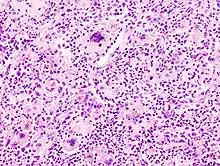

Foreign-body giant cell reaction to a suture. H&E stain.

Micrograph showing a foreign body engulfed by a giant cell. H&E stain.

Foreign body giant cell reaction to silicone leakage from breast implant. H&E stain.